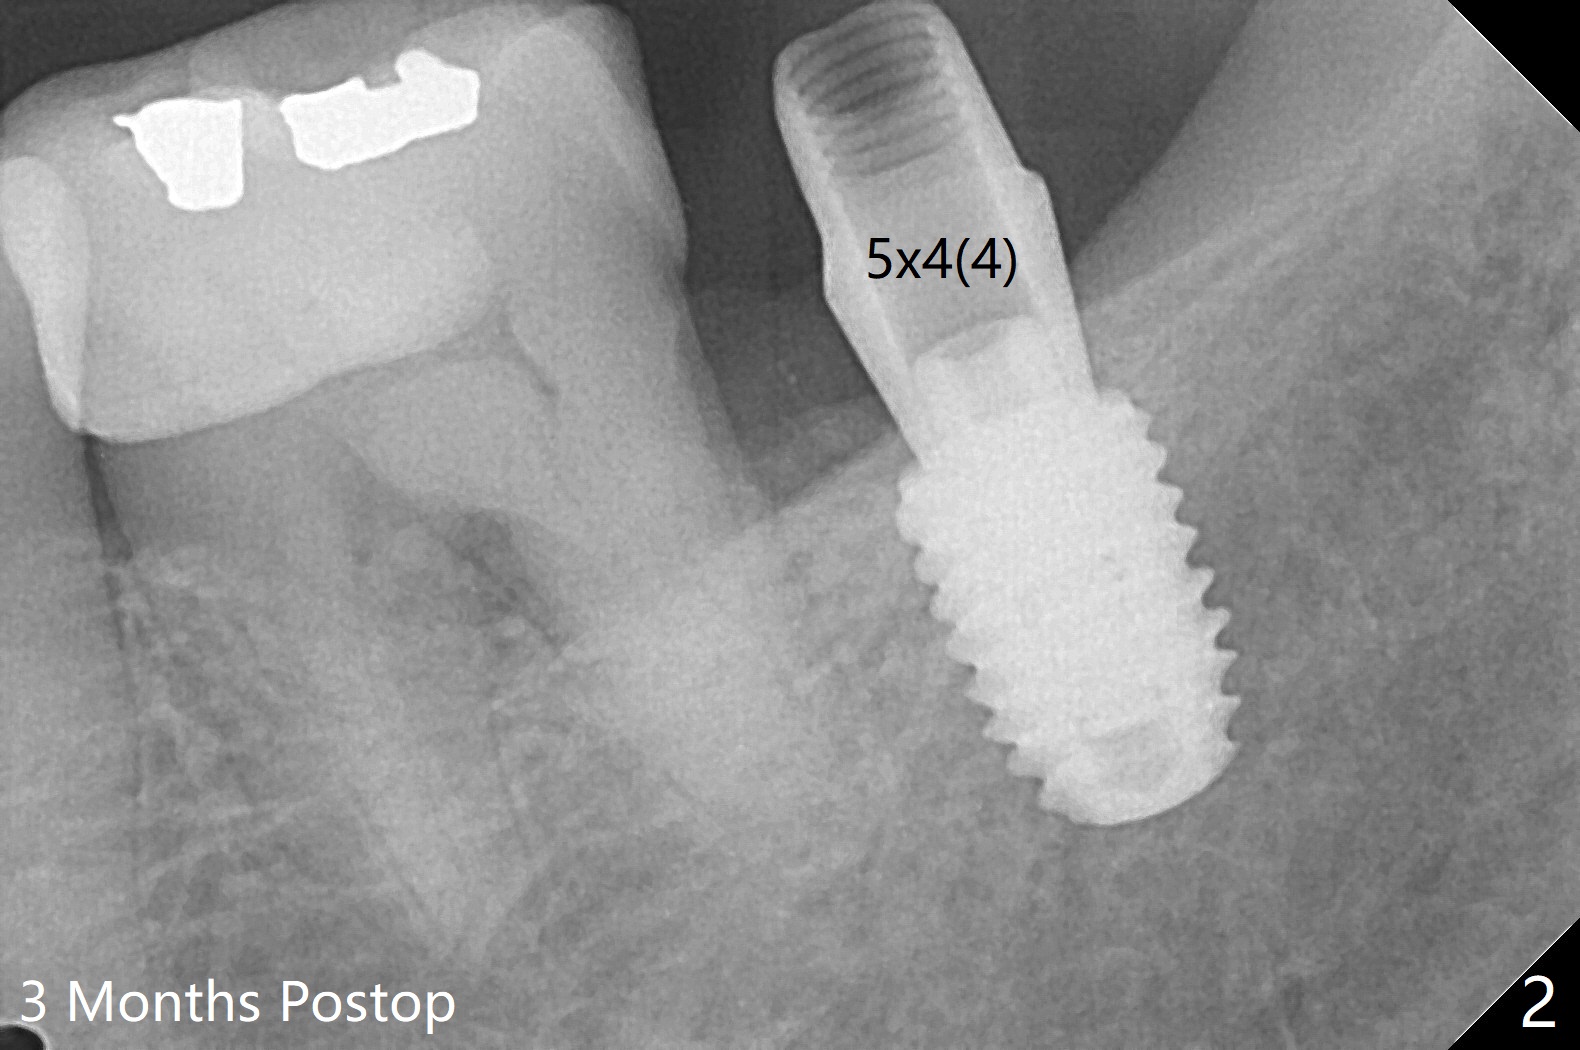

As expected, bone density is low at #31 during osteotomy. Underprep in depth (close to IAN) and diameter is done with satisfactory torque (~15 Ncm). What was not expected intraop is having to use one carpule of Septocaine in addition to Lidocaine. Postop PA shows why (closeness of the implant to IAN, Fig.1). The guide helps slightly subcrestal placement of the implant except lingual (equicrestal). Autogenous bone graft is placed, followed by sutures. Incision is initiated because of the narrow keratinized band. An IBS abutment seems to be completely seated in the IS implant (Fig.2). The gingiva is healthy at the time of impression.